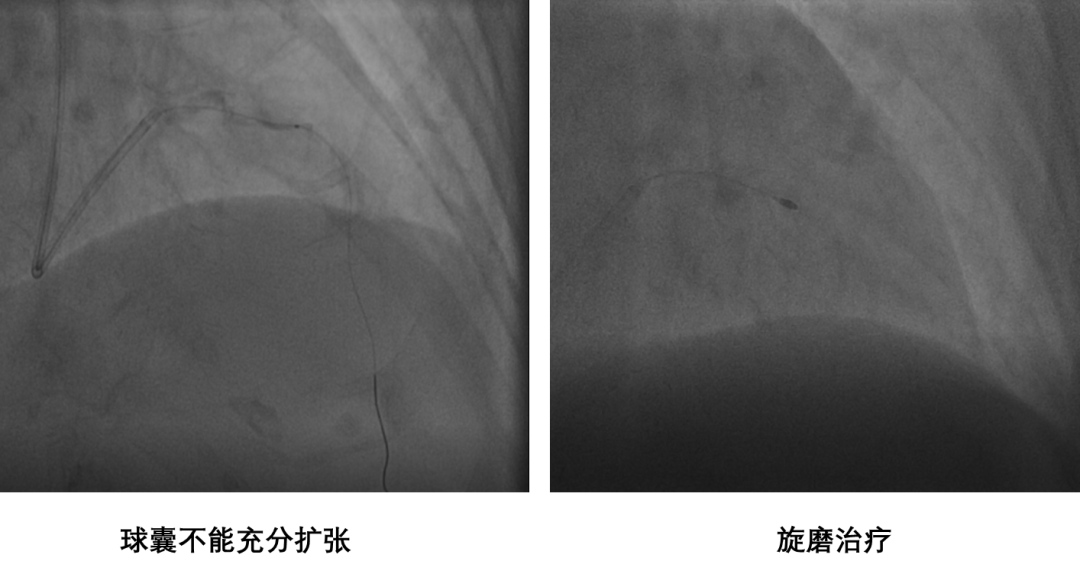

患者为85岁老年女性,以突发胸痛9小时入院。入院诊断为急性非ST段抬高型心肌梗死。入院后反复出现心绞痛发作,行急诊冠脉造影提示三支病变,前降支重度钙化,建议患者行冠脉搭桥手术治疗,患者及其家属表示拒绝。丛洪良教授在充分分析患者病情和冠脉病变特点后,决定在IABP的支持下行Shockwave冲击波球囊行碎石手术。

由于前降支病变钙化极其严重,多次使用球囊扩张后,IVUS导管仍不能通过病变,无法进行术前评估,Shockwave球囊也无法通过病变,决定先行旋磨治疗。

经1.5mm旋磨头旋磨8次后,旋磨头不能完全通过病变,而且患者出现顽固性无复流,经微导管多次给与腺苷、硝普纳以及欣维宁后前降支血流有所改善,但效果不明显,前壁导联心电图ST段抬高。随后使用2.5mm球囊到达病变后,多次加压扩张难以使钙化狭窄的部位充分扩张,立即使用Shockwave冲击波球囊行碎石手术。经过8个周期(80个脉冲)冲击波治疗后,IVUS证实钙化病变出现断裂,最终成功植入支架,达到理想的支架膨胀贴壁效果。